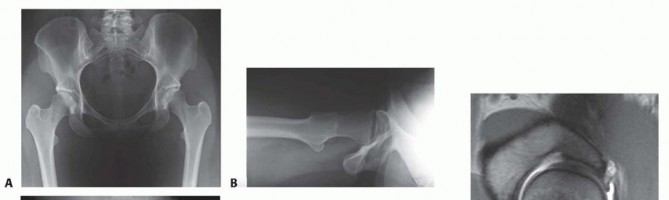

DEFINITION This chapter's focus is the use of pelvic osteotomies for acetabular reorientation for the treatme…